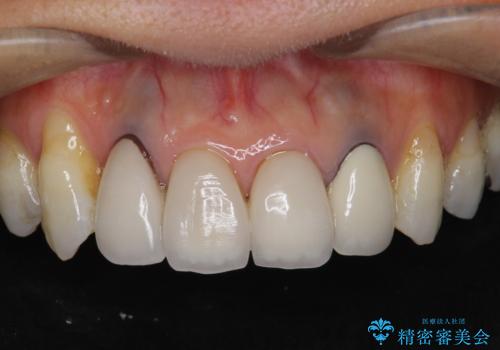

歯ぐきの黒ずみ クラウンやりかえによる改善